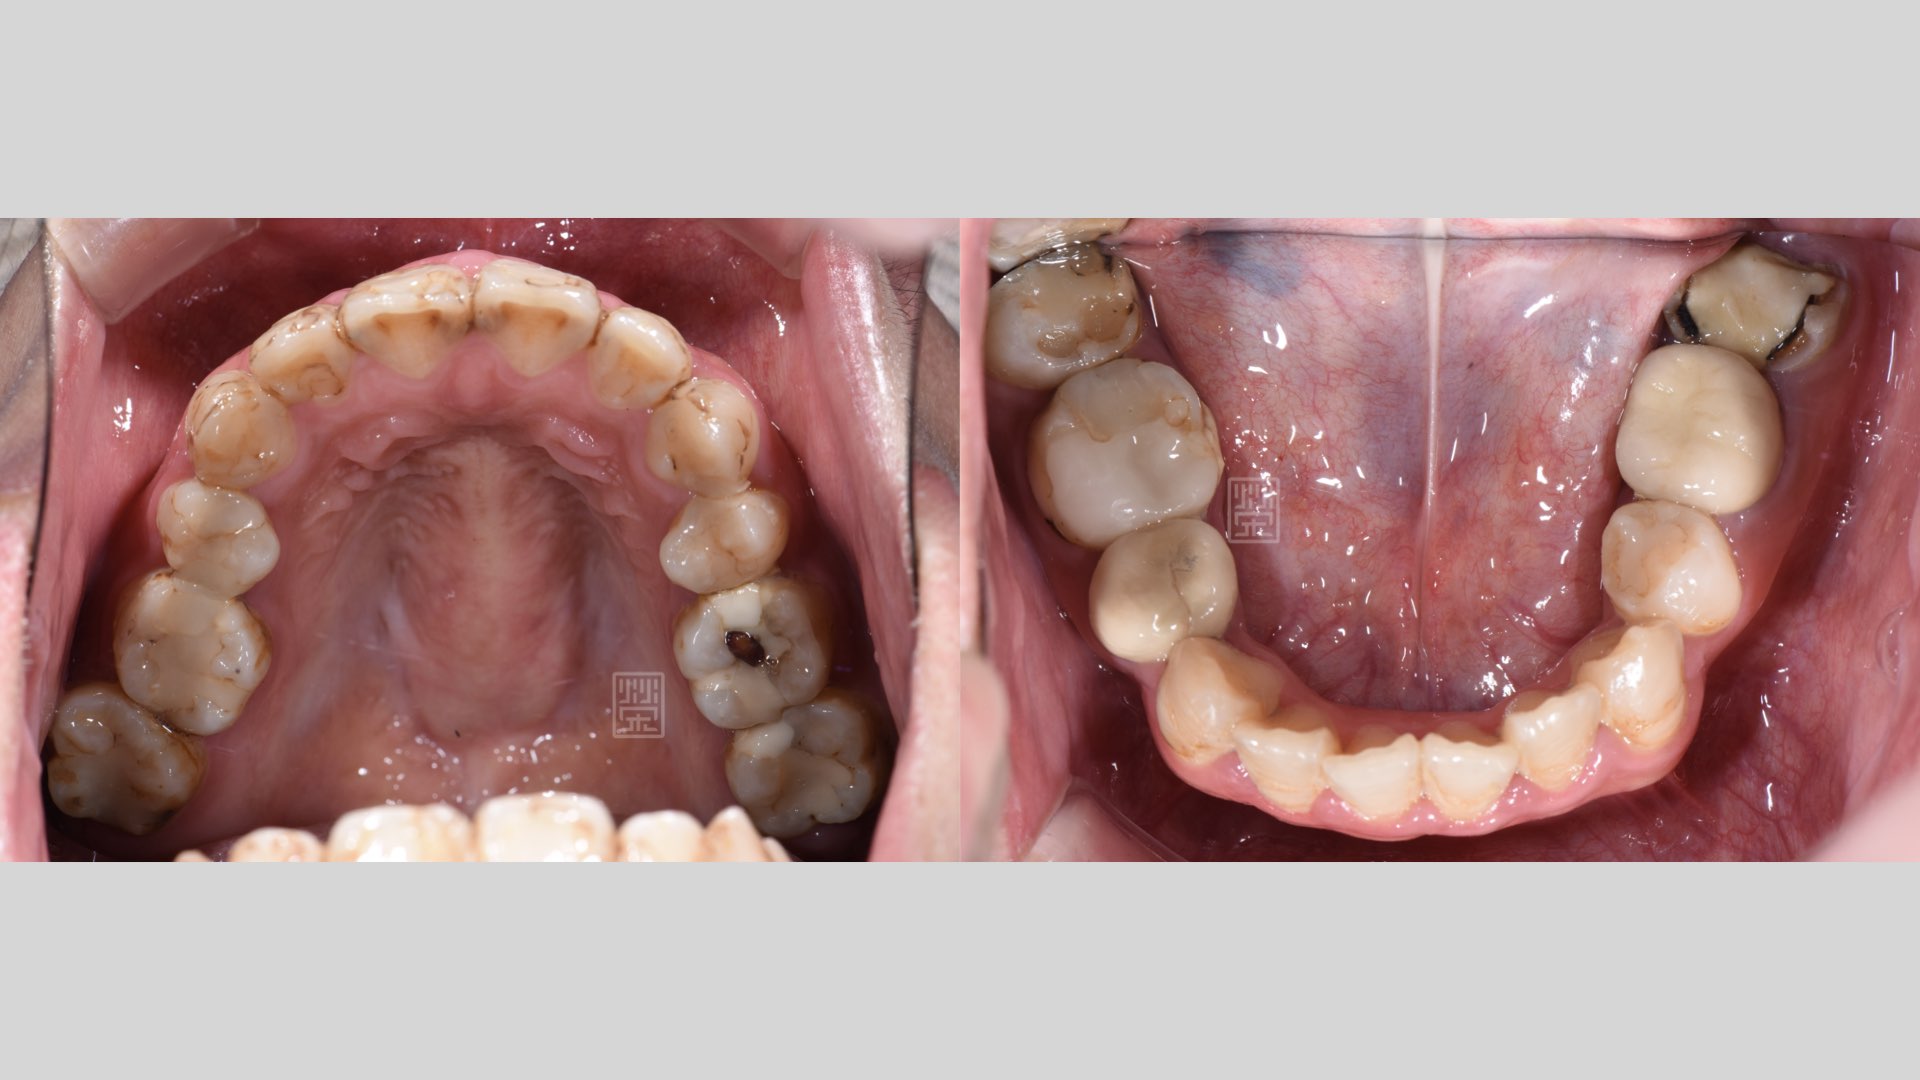

後牙蛀牙清除

後牙蛀牙清除後,牙髓受感染,MTA覆髓治療

後牙多次蛀牙填補